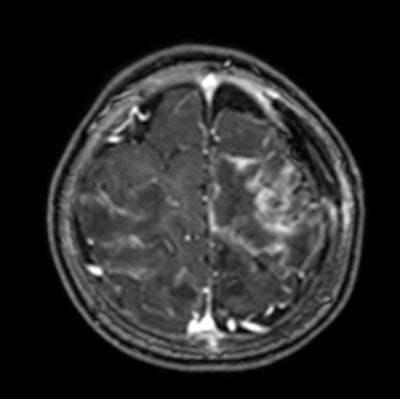

An axial T1-weighted MRI scan of a hydatid cyst. Clinical images courtesy of Dr. Carlos F. Ugas Chacape.

Contrast-enhanced T1-weighted MRI scan shows multiple abscesses due to free-living amebiasis (Balamuthia mandrillaris).

Neurocysticercosis is still prevalent but is decreasing in Peru, whereas free-living amebiasis is less common but has a rising prevalence and is often fatal without treatment. Toxoplasmosis remains a significant congenital infection in Latin America, and it's important to be aware of hydatid disease, malaria, toxocariasis, and strongyloidiasis.

"Parasitic brain infections persist in Peru, and primarily affect underserved children with poor access to medical care," Ugas said. "Neurocysticercosis is still relevant, and the radiological features and stages in children align with adults."

Free-living amebiasis is a growing concern, being rapidly progressive and often fatal without early intervention. Congenital toxoplasmosis remains prevalent, and the severe features are more prevalent in Latin America.

Radiologists play a vital role by making a timely diagnosis using MRI, improving outcomes, and guiding treatment. "Our call to action should be advocacy for improved sanitation, healthcare access, and education to combat these infections," he said.